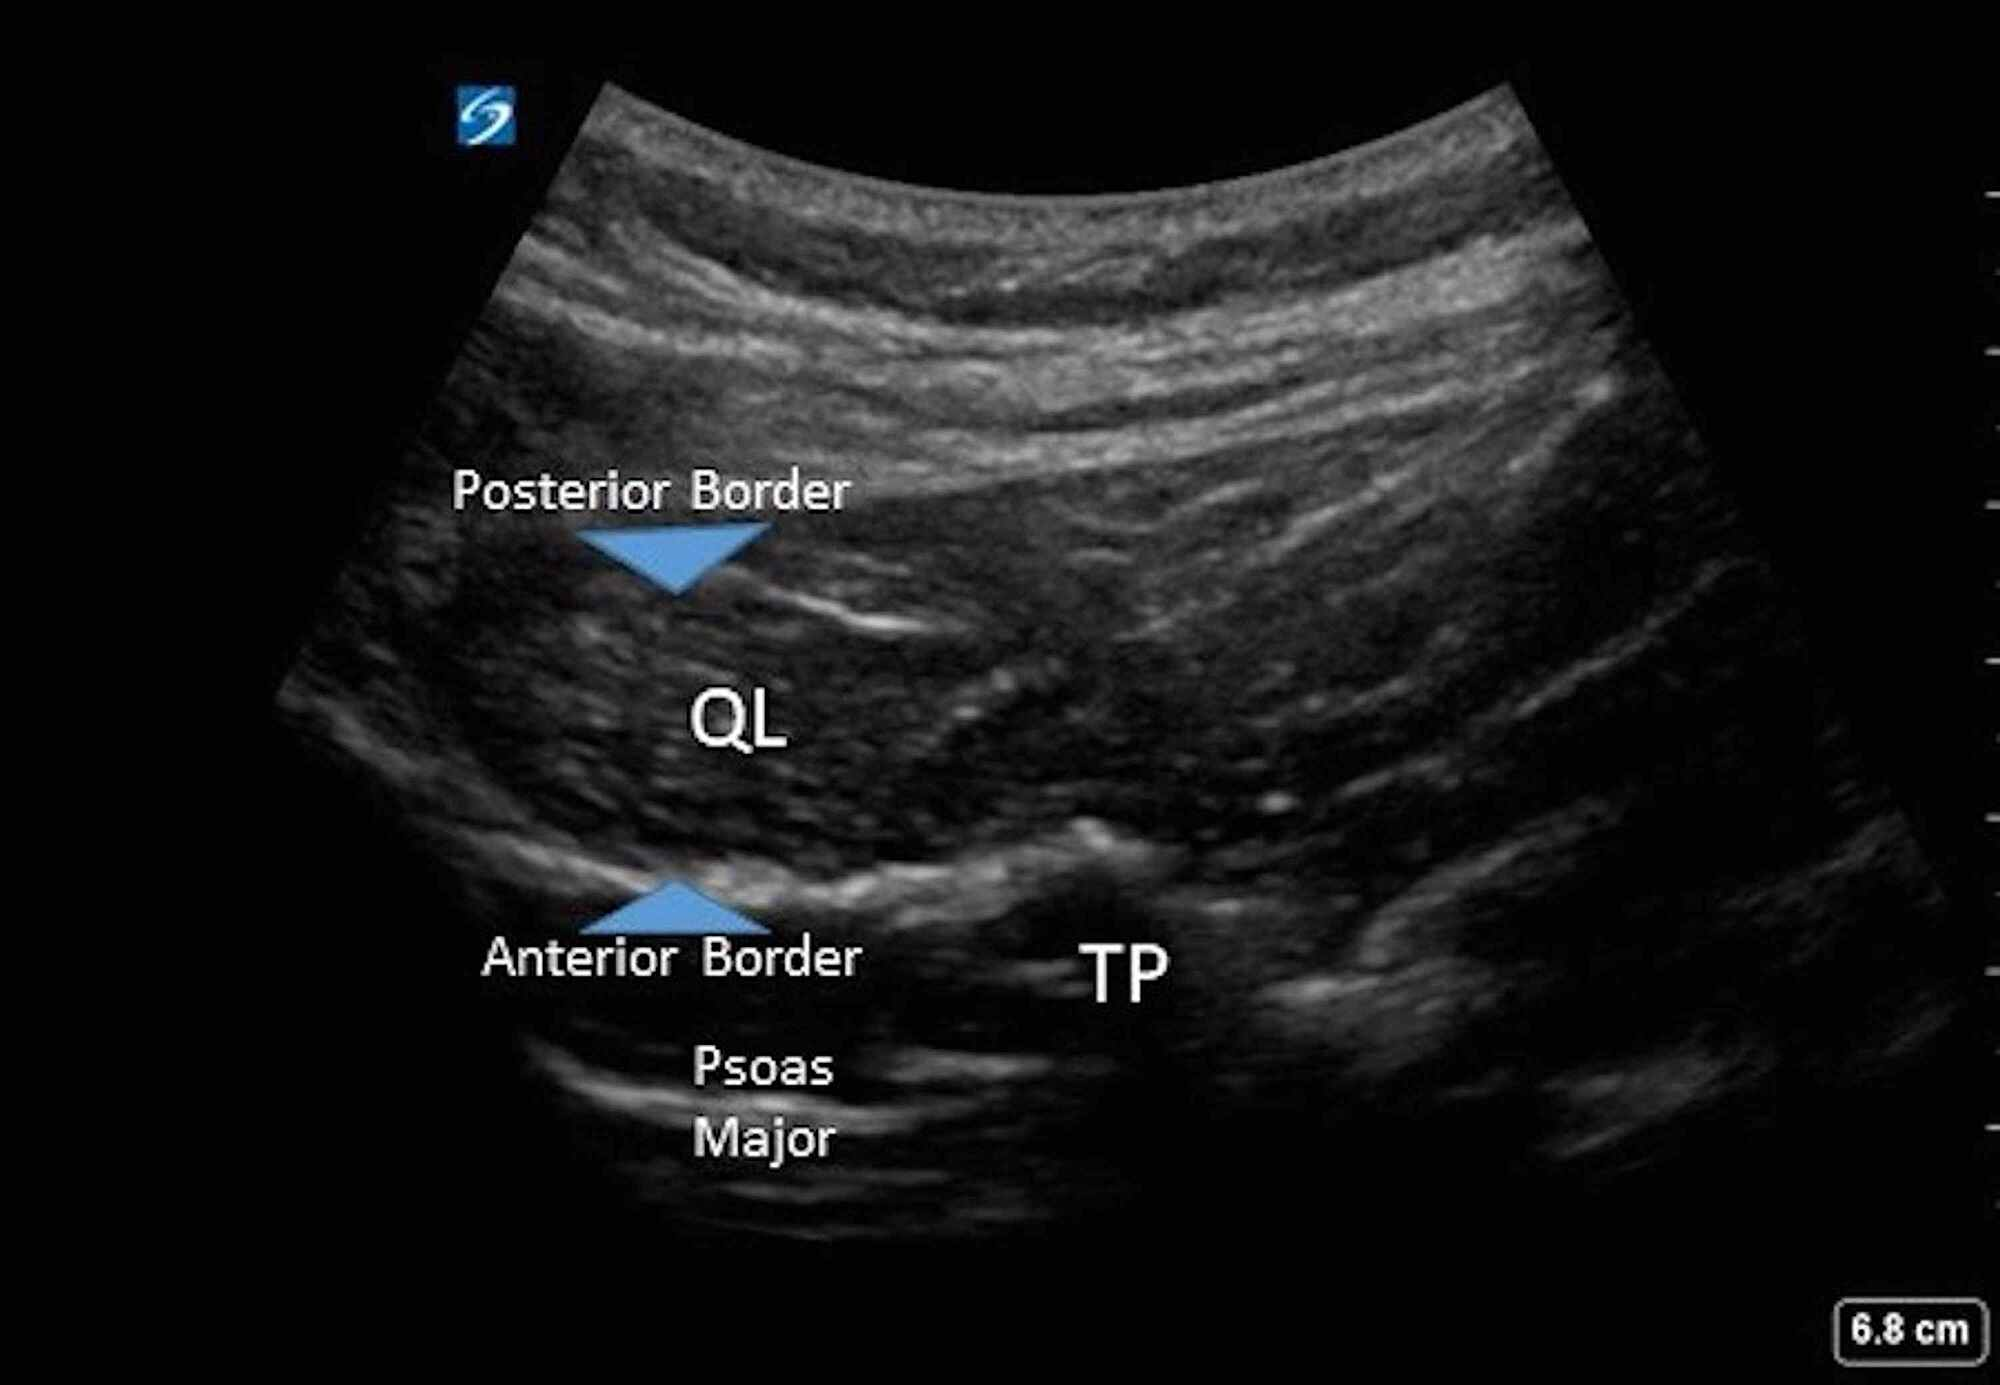

Sonographic anatomy of the QL block (QL Quadratus lumborum muscle, PM Ql Block Anatomy This activity reviews a recent variation of the tap block known as the quadratus lumborum block (qlb). The lateral ql block injects the local. Identify the indications for the quadratus. Anatomic view of quadratus lumborum (ql) block (anterior, lateral, and posterior). Psoas major muscle, and gray line: We need to know the anatomy of the. Currently, the ql block is. Ql Block Anatomy.